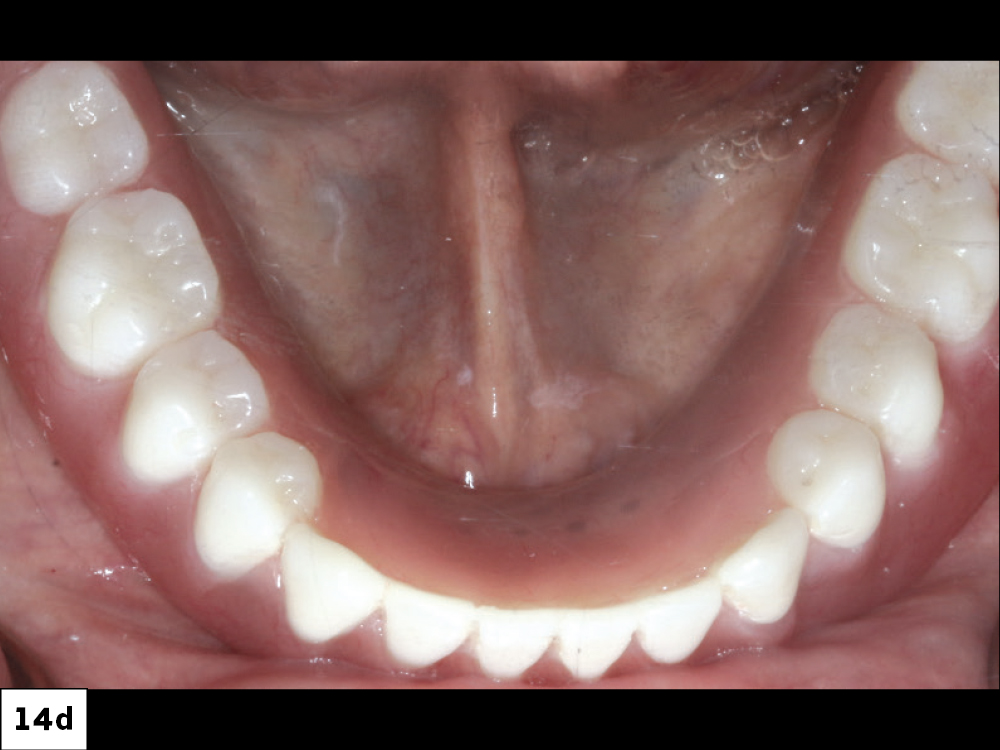

CASE REPORT NO. 1

Freestanding Locator Attachments

Overdentures offer the esthetics of traditional dentures with better retention.